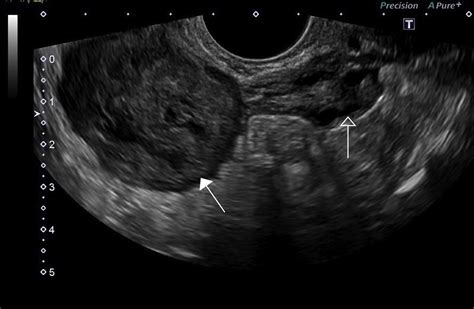

• Ultrasound: This imaging test uses sound waves to create images of the uterus and can help identify the size and location of fibroids.